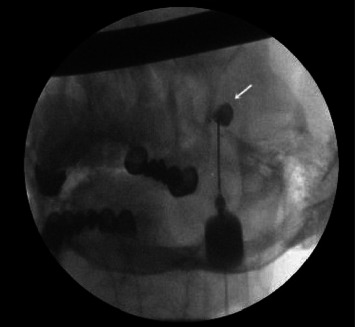

Abstract Image